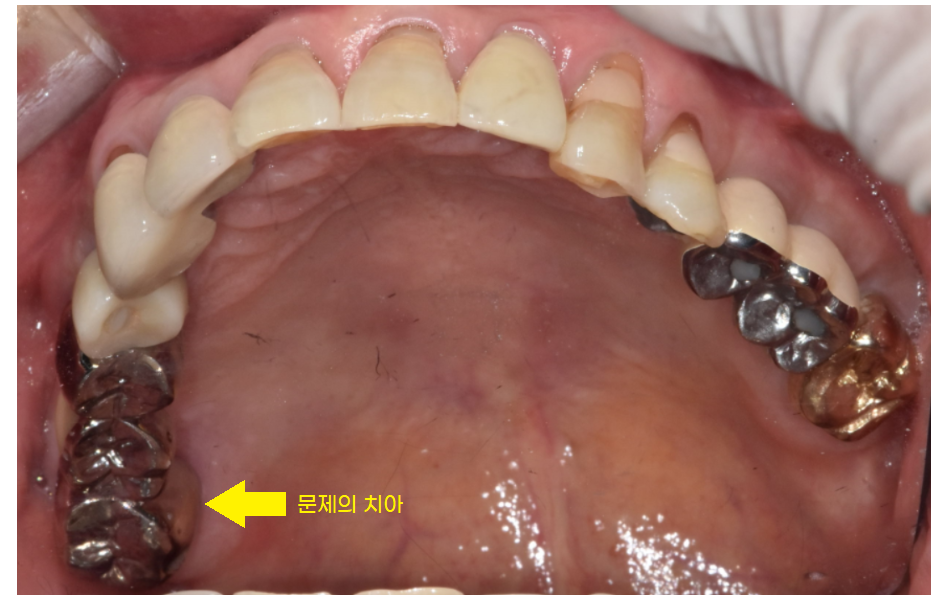

요즘은 잘 쓰지 않는

은색 치아인걸보니

치아를 씌운지 정말 오래되셨나봅니다.

우선 예전에 씌운 이를 벗겨내봐야

내부 상태를 정확히 알 수 있어서

보철물을 벗겨보았는데요.